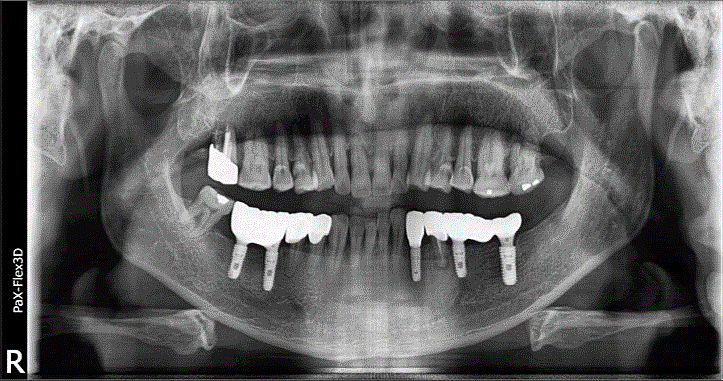

68세 남성

(전) 2021-11-05, (후) 2022-08-26

임플란트/크라운 시술 후

음식 섭취뿐만 아니라, 심미적인 개선으로

삶의 질이 높아진 환자분의 사례

잇몸뼈 부족으로 상악동거상술을 통한 뼈이식 진행한 환자분의 x-ray